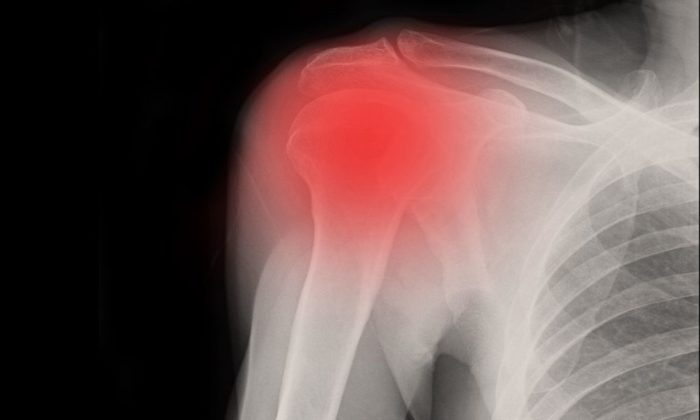

A frozen shoulder usually occurs when the soft tissues become inflamed, typically due to injuries from overuse such as bursitis or tendinitis of the rotator cuff. Inflammation causes pain and becomes worse with movement. When the shoulder becomes immobilized, the connective tissue surrounding the glenohumeral joint — the joint capsule — thickens and contracts, losing its ability to stretch. Trying to avoid the pain caused by moving the shoulder leads to further contraction of the capsule. The humerus now has less space in which to move, and the joint may lose its lubricating synovial fluid. In severe cases, bands of scar tissue (adhesions) form between the joint capsule and the head of the humerus, hence limiting the shoulder’s range of motion.

When diagnosing a frozen shoulder, you will need to consult with your doctor in order to discuss your symptoms and review your medical history. Your doctor will need to conduct a physical examination of your arms and shoulders. The doctor will try to move your shoulder in all directions to check the range of motion and if there is pain with the movement. During this exam, they check your “passive range of motion.” The doctor will also watch you move your shoulder to see your “active range of motion.” A person suffering from a frozen shoulder has limited range in both active and passive motion. X-rays of the shoulder will also be needed to make sure the cause of the symptoms is not due to other conditions such as arthritis. Advanced imaging tests, such as magnetic resonance imaging (MRI) and ultrasound, are usually not necessary to diagnose frozen shoulders. MRI and ultrasound results may be taken to look for other problems, such as a rotator cuff tear.